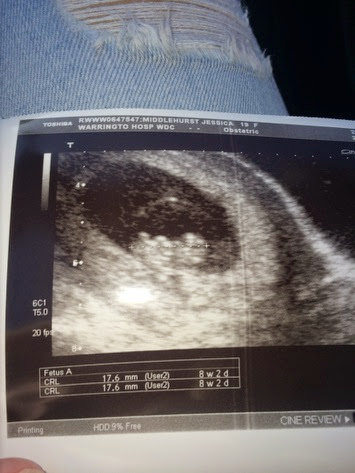

Baby scan for my eldest son Jonathan and his  partner to find out if all's well and what sex their second little one is.well it's another little girl, awww (first pic)

And then middle son Matthew and his partner Jessica had their first scan for their first baby...have to wait to find out the sex though.